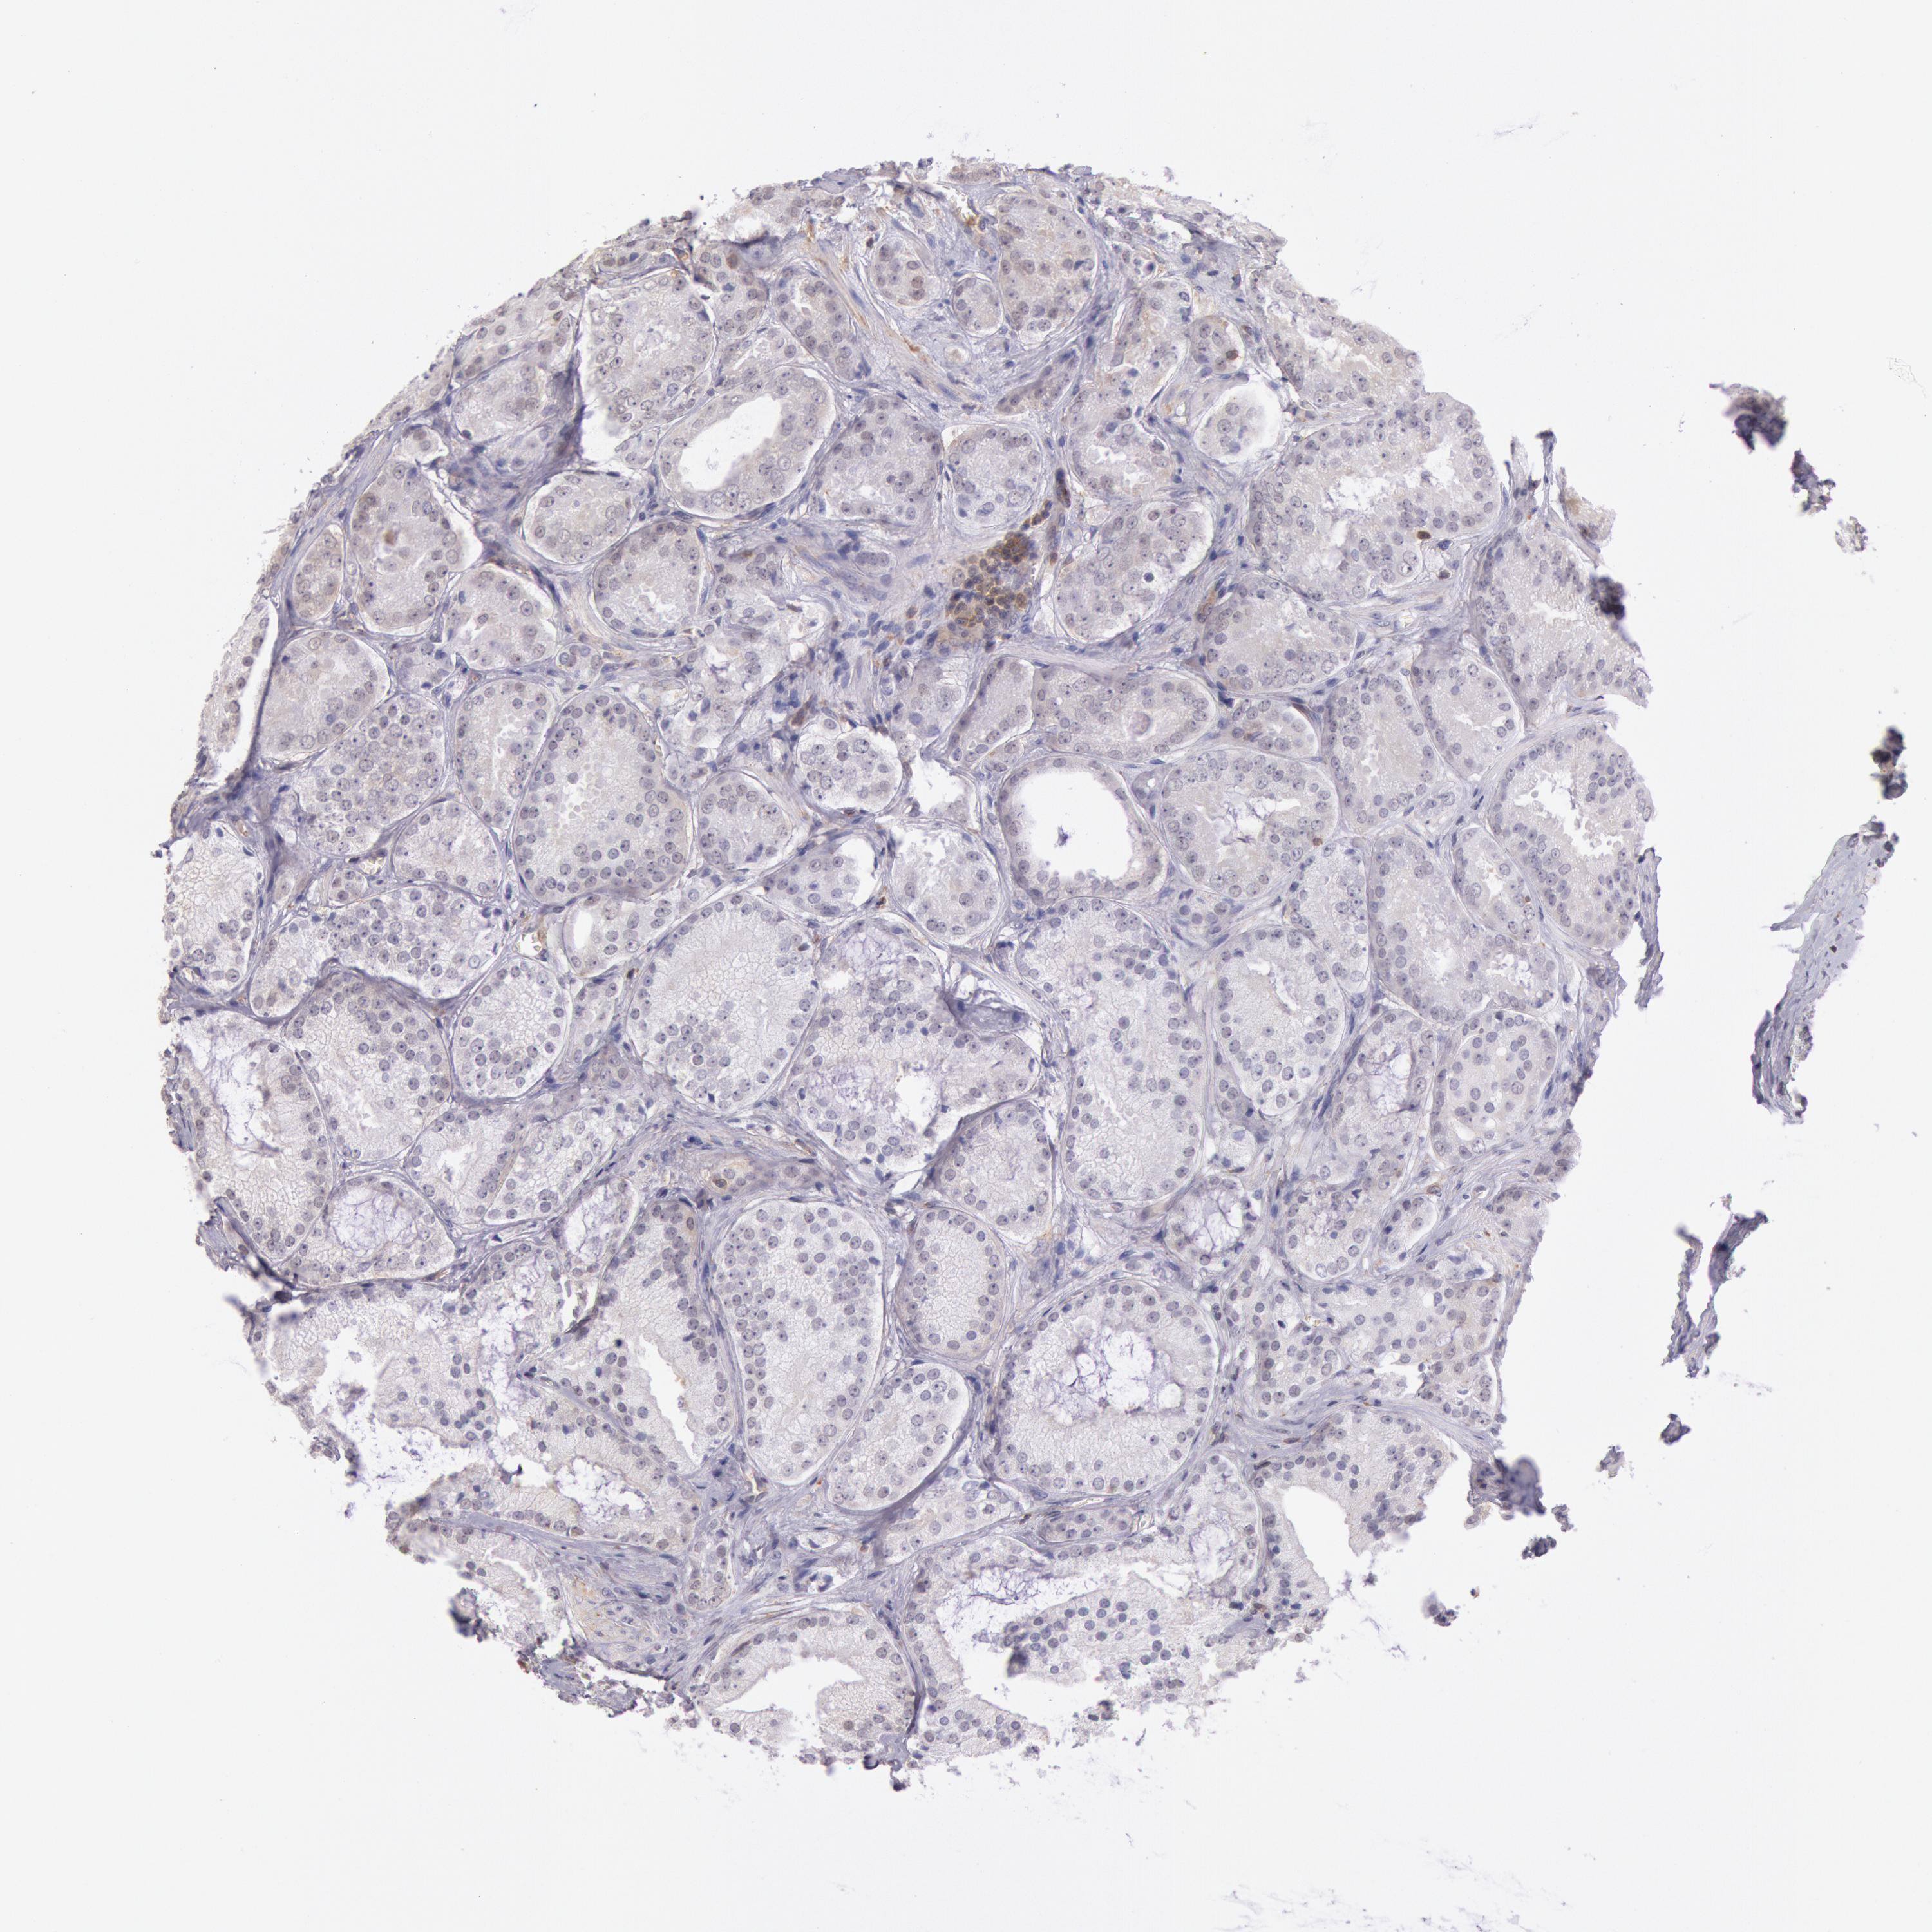

PROSTATE CANCER - Protein expressioni

A mouse-over function shows sample information and annotation data. Click on an image to view it in a full screen mode. Samples can be filtered based on level of antibody staining by selecting one or several of the following categories: high, medium, low and not detected. The assay and annotation is described here.

Antibody stainingi

Antibody staining in the annotated cell types in the current human tissue is reported as not detected, low, medium, or high, based on conventional immunohistochemistry profiling in selected tissues. This score is based on the combination of the staining intensity and fraction of stained cells.

Each image is clickable and will lead to virtual microscopy that enables deeper exploration of all samples and also displays staining intensity scores, fraction scores and subcellular localization as well as patient and tissue information for each sample.

Antibody HPA001275

Antibody CAB017442

Staining

High

Medium

Low

Not detected

Intensity

Strong

Moderate

Weak

Negative

Quantity

>75%

75%-25%

<25%

None

Location

Nuclear

Cytoplasmic/membranous

Cytoplasmic/membranous,nuclear

Adenocarcinoma, Medium grade

Adenocarcinoma, Low grade

Adenocarcinoma, High grade